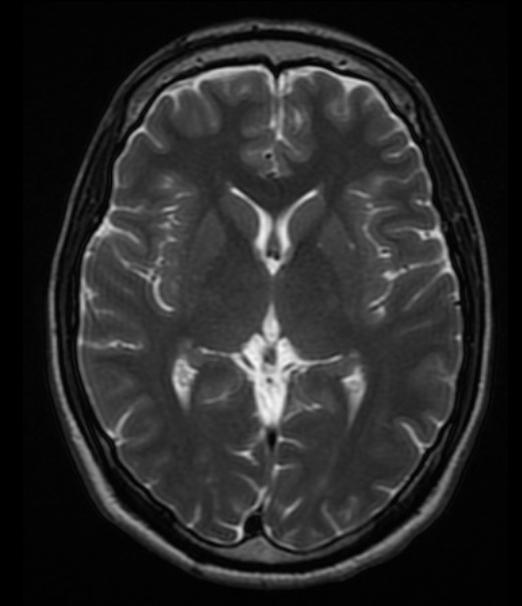

不同的策划内的氢原子核,其T2弛豫时间也不同。比如,脑策划的T2弛豫时间要短于脑脊液。基于T2弛豫生成的脑图像称为T2加权图像(T1 weighted image)。

T2图像无法区分灰质白质,脑脊液呈亮白色